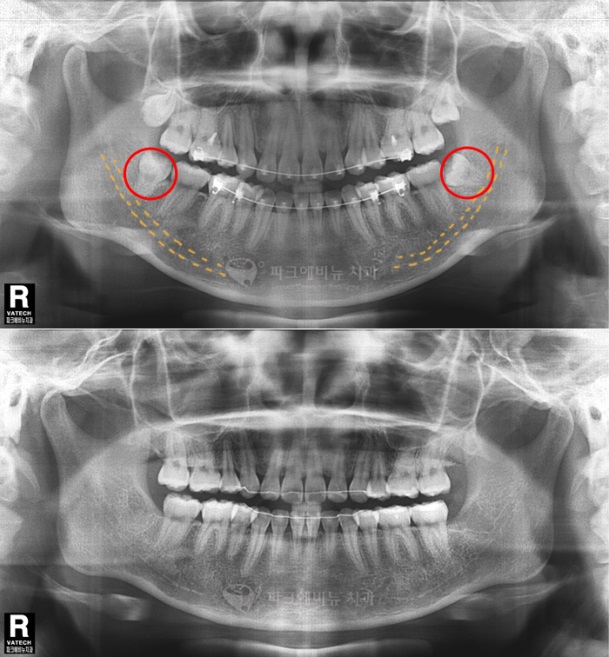

回答1 。智齿在不充分的空间里长,大部分不容易长牙也有疼痛。如果水平或倾斜长大的话会动周围牙齿和牙齿神经会受疼痛。其外,牙齿不平衡的长了智齿后面夹饮食物会引发牙周病等。

回答2。下颚发达就没有影响到周围牙齿和下颚,正常的出牙的话拔牙就好了。现在没有什么反应就放弃的话以后会有更大的问题。

回答3。也有不出智齿的人。但是已经出的智齿埋伏本人不知不觉长大会有问题必须在牙科检查以后拔牙是最好的。